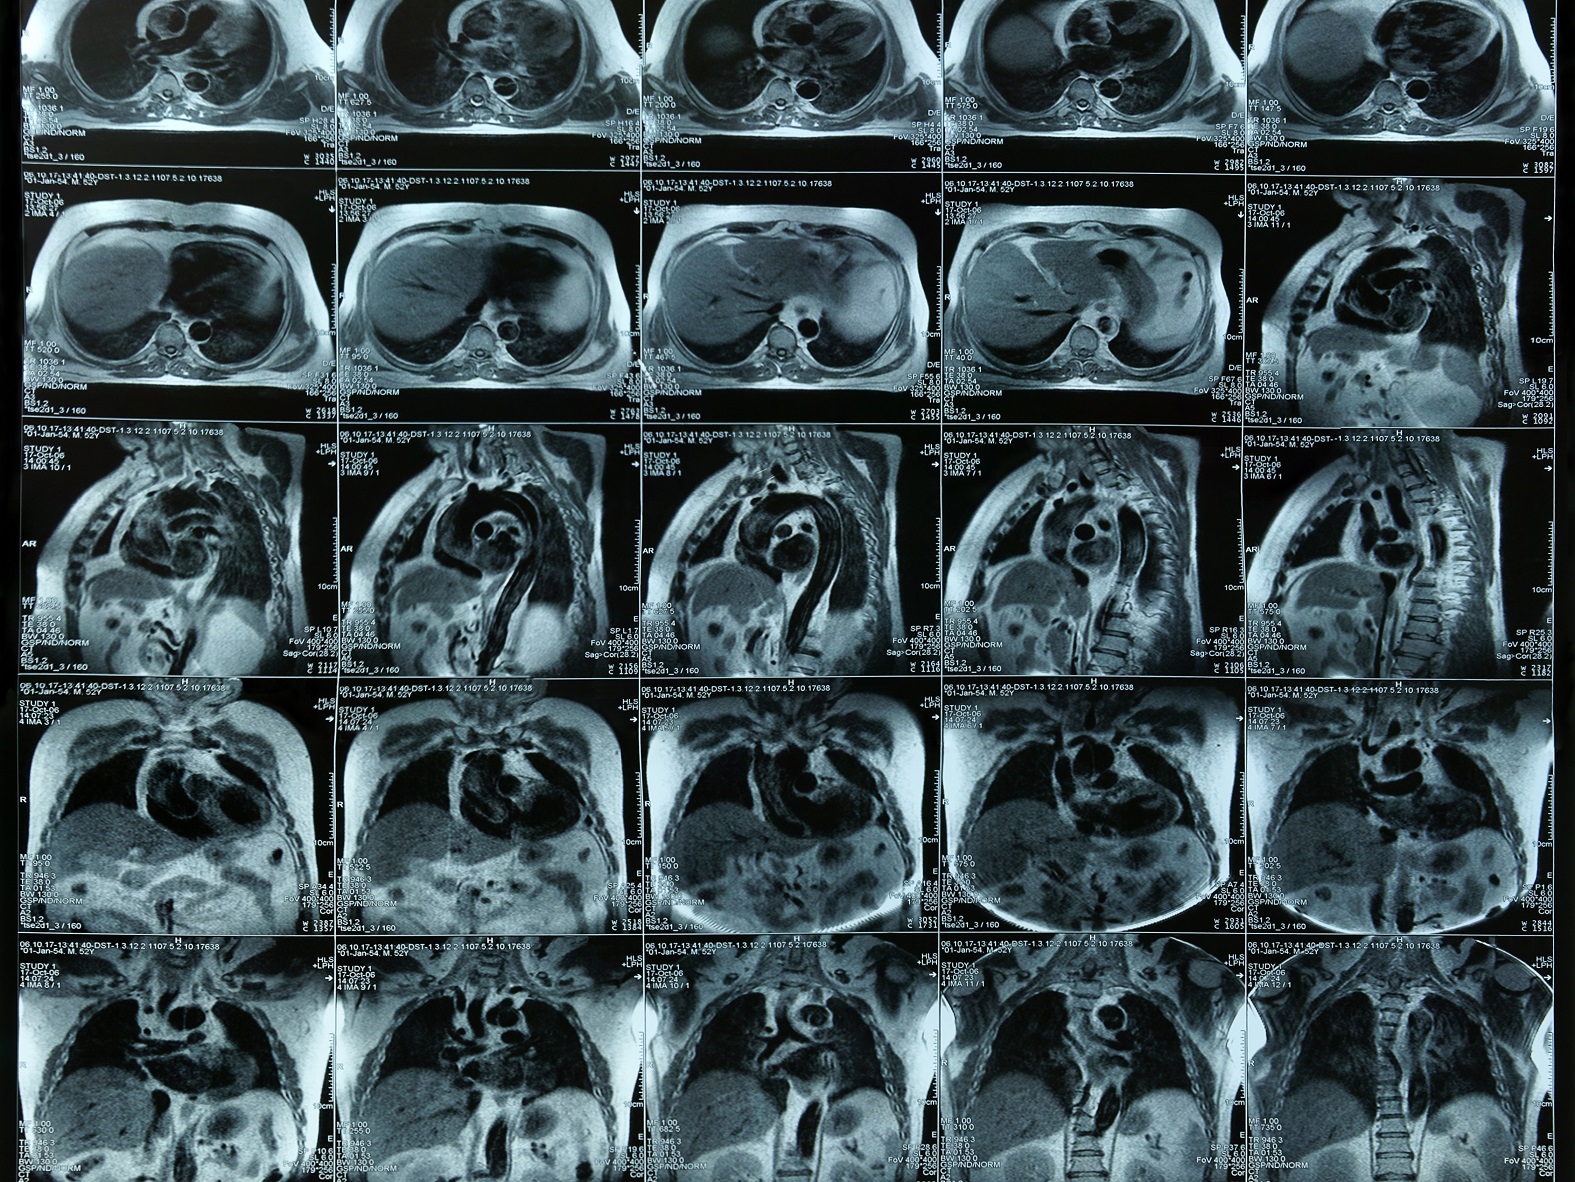

What is an MRI of the chest, abdomen or pelvis?

Magnetic resonance imaging, or MRI, is a method of producing detailed pictures of organs and body tissues by exposing a patient to radio waves in a strong magnetic field. The field is measured and analyzed by a computer, which forms two- or three-dimensional images that may be viewed on a monitor. Because it uses radio waves and a magnetic field rather than x-rays, there is no exposure to radiation. An MRI of the chest, abdomen or pelvis provides information on the heart and lungs, abdomen and pelvis that may not be detected by an x-ray, ultrasound or computed tomography (CT scan).

An MRI is often used to clarify previous x-rays or CT scans. Your doctor might recommend an MRI of the chest to detect abnormal growths including cancer and the stages of cancer growth. An MRI of the chest also can reveal diseased heart valves, disorders of the ribs and sternum and early breast cancer.